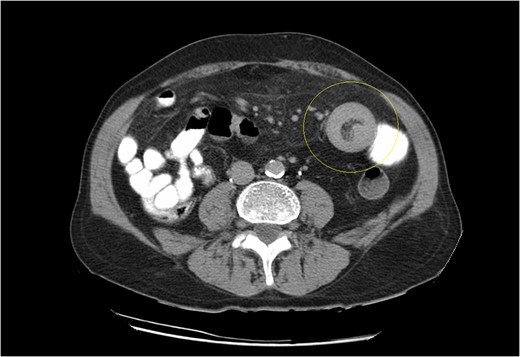

CT scan demonstrating the typical ‘doughnut’ sign of bowel intussusception.

(a, b) Small bowel intussusception located in the proximal jejunum.

Computed tomography is the modality of choice for diagnosis of an intussuscepted bowel loop, with a sensitivity and specificity of ~80% and 100%, respectively. Depending on sagittal or axial view, findings may include the presence of concentric rings due to duplication of small bowel layers (‘doughnut’ or ‘target’ sign), or a sausage shaped mass [3, 5, 6]. U/S scan is also useful for identification of intussuscepted bowel with the typical ‘target sign’ [6]. Diagnosis is usually set intraoperatively, because of the nonspecific clinical symptoms and non-pathognomonic radiological findings.